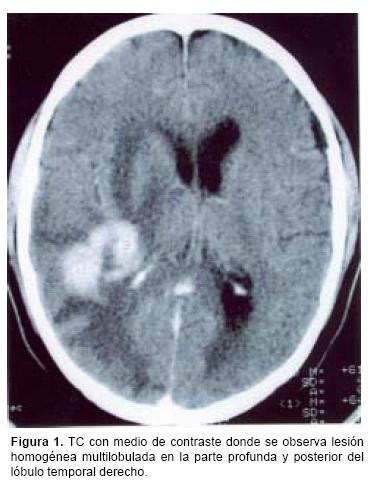

En los estudios de imagen, el LPSNC se manifiesta por lesiones únicas o múltiples, generalmente en la región peri–ventricular y éstas muestran diferentes patrones de reforzamiento con el medio de contraste, dado que tiende a ser anular en casos de pacientes con inmunodeficiencia, mientras que es homogéneo en los IC. Sin embargo, aun cuando los estudios de imagen sean altamente sugestivos del diagnóstico, es necesaria la confirmación histológica. Debido al tamaño y la localización de la mayoría de las lesiones en la profundidad del parénquima cerebral, es innegable que el mejor método para obtener el diagnóstico es la biopsia por estereotaxia.12,13 Sin embargo, este procedimiento presenta algunos problemas: en primer lugar, en ocasiones no es posible obtener una cantidad suficiente de tejido para efectuar el diagnóstico correcto; en segundo lugar, la mayoría de los pacientes con estas lesiones ya han sido tratados con esteroides antes de la cirugía, medicamentos que han demostrado tener un efecto citotóxico en los linfomas cerebrales, condicionando una reducción en el tamaño o hasta desaparición del tumor. Este hecho dificulta no sólo el diagnóstico histológico sino la toma de biopsia en sí misma.

La distribución por sexo de los 22 pacientes, fue equitativa (Cuadro I) con un promedio de edad de 65 años (límites entre 43 y 92 años). Cinco pacientes refirieron antecedentes neoplásicos heredofamiliares en rama directa: dos carcinomas cervicouterinos, dos adenocarcinomas de pulmón y un carcinoma de células gigantes. En un solo paciente se encontró antecedentes personales de neoplasia, por melanoma diagnosticado 10 años antes. El tiempo promedio entre la aparición del primer síntoma y la hospitalización fue de 80 días (límites entre 7 y 730), el cual fue con mayor frecuencia cefalea asociada a déficit neurológico focal. Un paciente presentó síntomas inespecíficos, tales como febrícula y alteraciones gastrointestinales antes del inicio del cuadro clínico, sin asociación al padecimiento neurológico. El promedio de calidad de vida de acuerdo a la escala de Karnofsky26 fue de 62.7 años. Los estudios radiológicos mostraron en cuatro pacientes lesiones múltiples, mientras que en el resto fueron lesiones únicas. La localización de cada lesión fue como sigue: 21 en los hemisferios cerebrales (ocho parietales, seis frontales, cuatro temporales y tres occipitales), seis en los núcleos basales, cuatro en el cuerpo calloso y uno en el tallo cerebral. En la tomografía computada las lesiones se apreciaron isodensas con discreta tendencia a la hiperdensidad y con un reforzamiento regular y marcado a la administración del medio de contraste (Figura 1). En la resonancia magnética, las lesiones aparecieron como iso o discretamente hipointensas en T1, con evidente y homogéneo reforzamiento con la aplicación del medio de contraste (Figura 2); en la fase T2 la mayoría de las lesiones eran hiperintensas, acompañándose de un marcado edema circundante. El tamaño promedio de los tumores fue de 22 mm (límites entre 3 y 57 mm), localizándose la mayoría de ellas en la región periventricular o subcortical, adyacentes a la circulación del líquido cefalorraquídeo; en el cuerpo calloso se ubicaban principalmente en el esplenio (Figura 3).